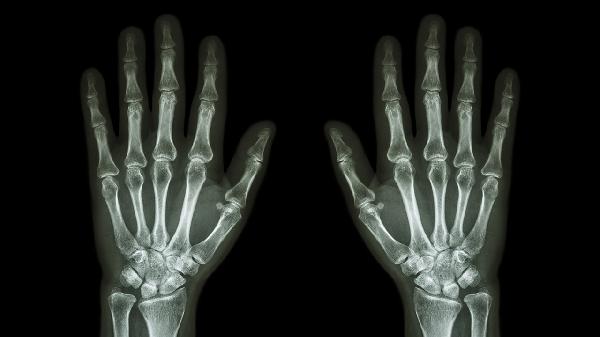

手指关节囊损伤3个月后仍疼痛可能由关节囊修复不全、慢性炎症、肌腱粘连、创伤性关节炎等原因引起,可通过物理治疗、药物治疗、康复训练、手术松解等方式缓解。

1. 关节囊修复不全

损伤后组织修复不良可能导致持续性疼痛,表现为活动时关节僵硬。建议进行热敷和关节活动度训练,必要时使用塞来昔布胶囊、双氯芬酸钠缓释片等抗炎药物。

2. 慢性炎症

长期炎症反应会刺激周围神经末梢,疼痛特点为持续性钝痛。可尝试超声波治疗,配合洛索洛芬钠片、依托考昔片等非甾体抗炎药控制炎症。

3. 肌腱粘连

损伤后制动可能导致肌腱与周围组织粘连,表现为活动受限伴疼痛。需进行专业康复手法松解,严重时可考虑关节镜下粘连松解术。

4. 创伤性关节炎

关节面损伤可能继发退行性改变,疼痛随负重加重。可关节腔注射玻璃酸钠,口服硫酸氨基葡萄糖胶囊保护软骨。

建议避免手指过度负重,定期进行温水浴和轻柔的关节活动,若保守治疗无效需及时复查影像学评估关节结构。